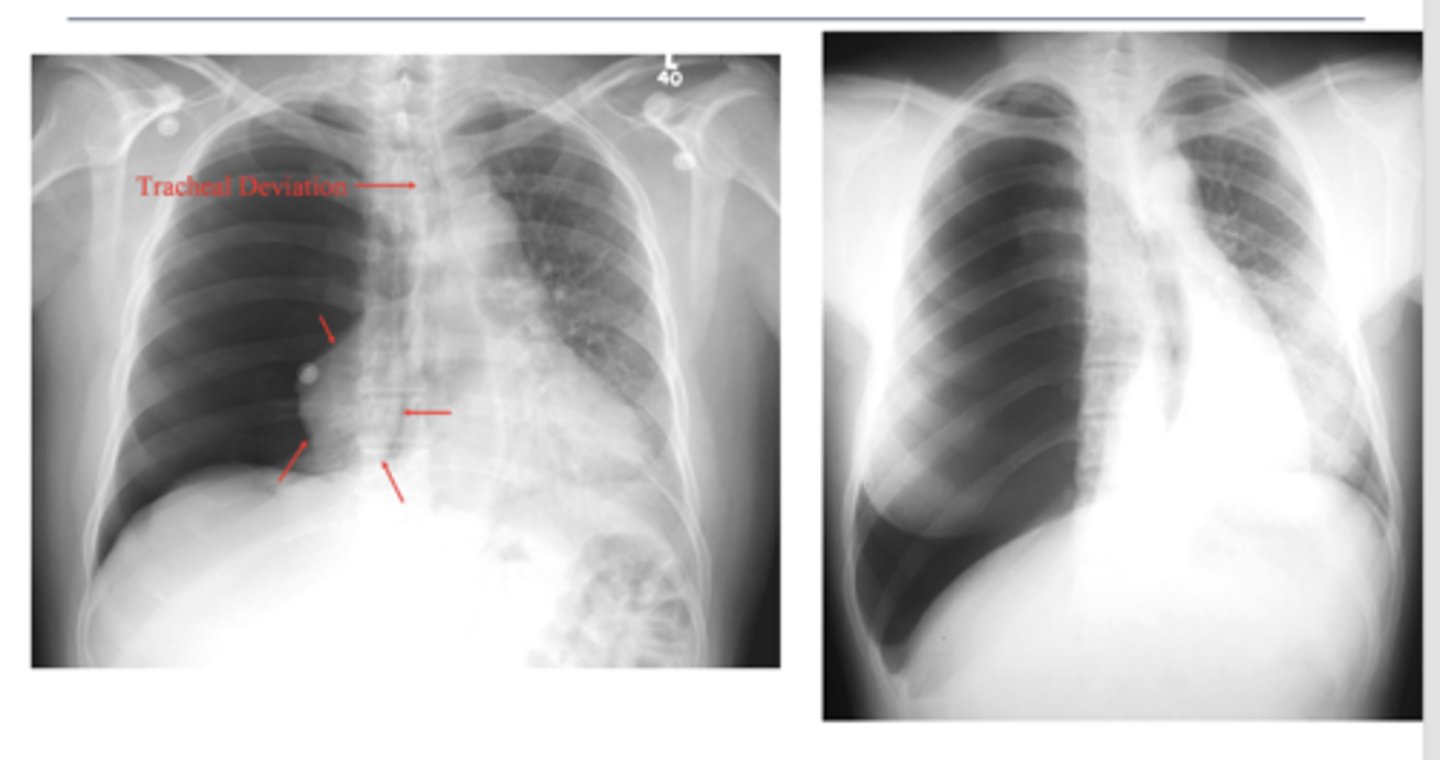

atelectasis - R lung collapse

--note: collpased lung pulling mediastinum towards R

oAir in the pleural space (pneumothorax) is usually seen in the apices if the patient is upright.

Seen as an area of no vascularity and a thin white line representing the visceral pleura

**air has no density (so air will show up as darker)

Shift of mediastinum

-if you're able to see t-spine in view, heart is not in the right place, likely laterally shifted

-hemidiaphragm

L sided moderate pneumothorax

-mediastinal shift

-less density (darker)

-sharp line if non-tension pneumothorax

Seems like biggest difference is shift of mediastinum